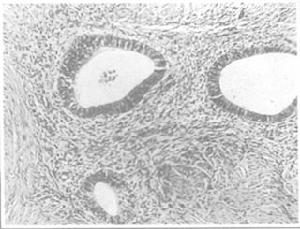

子宮腺肌病組織像病理:子宮多呈均勻增大,但很少超過12周妊娠子宮大小。子宮內病灶有瀰漫型及局限型兩種,一般為瀰漫性生長,且多累及後壁,故後壁常較前壁厚。剖開子宮壁可見其肌層明顯增厚且硬,剖面無肌瘤時所見到的那種明顯且規則的鏇渦狀結構,僅在肌壁中見到粗厚的肌纖維帶和微囊腔,腔中偶可見陳舊血液。少數子宮內膜在子宮肌層中呈局限性生長形成結節或團塊,類似肌壁間肌瘤,稱子宮腺肌瘤。腺肌瘤不同於肌瘤之處在於其周圍無包膜存在,故與四周的肌層無明顯分界,因而難以將其自肌層剝出。鏡檢見肌層內有呈島狀分布的子宮內膜腺體與間質。由於異位內膜細胞屬基底層內膜,對卵巢激素、特別是對孕激素不敏感,故異位腺體常處於增生期,僅偶爾見到局部區域有分泌期改變。